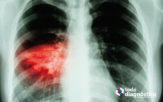

Precisión del diagnóstico de cáncer

Hablemos del diagnóstico de cáncer La detección temprana del cáncer es una de las oportunidades…